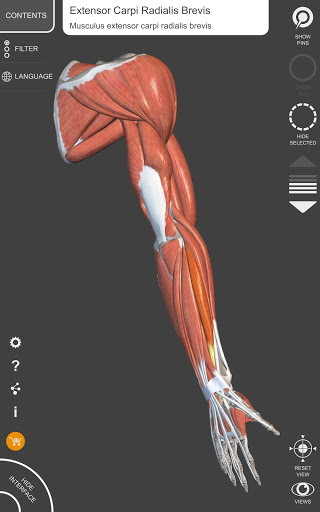

"Anatomy 3D Atlas" vous permet d'étudier l'anatomie humaine de manière simple et interactive.

Grâce à une interface simple et intuitive, il est possible d'observer chaque structure anatomique sous n'importe quel angle.

Les modèles anatomiques 3D sont particulièrement détaillés et avec des textures jusqu'à une résolution de 4k.

• Système musculo-squelettique

• Faites pivoter et zoomez chaque modèle dans l'espace 3D

• Option pour masquer ou isoler un ou plusieurs modèles sélectionnés

• Visualisation des muscles à travers des niveaux de couches depuis les plus superficielles jusqu'aux plus profondes

• En sélectionnant un modèle ou une épingle, le terme anatomique associé apparaît

• Description des muscles : origine, insertion, innervation et action